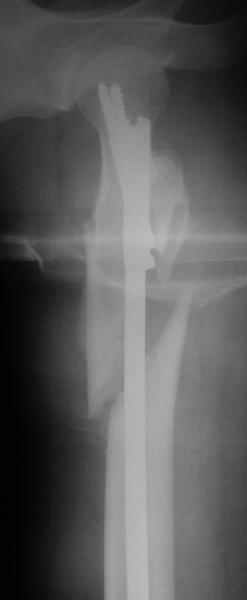

Другое наблюдение:Мужчина, 1957 г.р. Травма в результате ДТП 12.09.04г.

Диагноз: Закрытый оскольчатый подвертельный перелом правой бедренной кости со смещением отломков, оскольчатый перелом большого вертела, отрывной перелом малого вертела.Сопутствующие заболевания: Язвенная болезнь желудка, ремиссия.

Mike Shnider 17 Сентябрь 2004, 22:59

Все зависит, коллега,от оборудования, которым Вы обладаете.Имеет место метафизарный нестабильный перелом - отсюда и выбор фиксации-это может быть и Gamma nail,Recon nail,да на худой кончик пойдет и Richards DHS или L-plate.Сможете прихватить lesser вертел винтом - чудненько, а не сможете- то футбола не будет,а так по жизни не особенно помешает.

Предлагаю накостный ОС Г-образной пластиной, возможно в сочетании с 1-2 отдельно введенными винтами для фиксации крупных фрагментов.